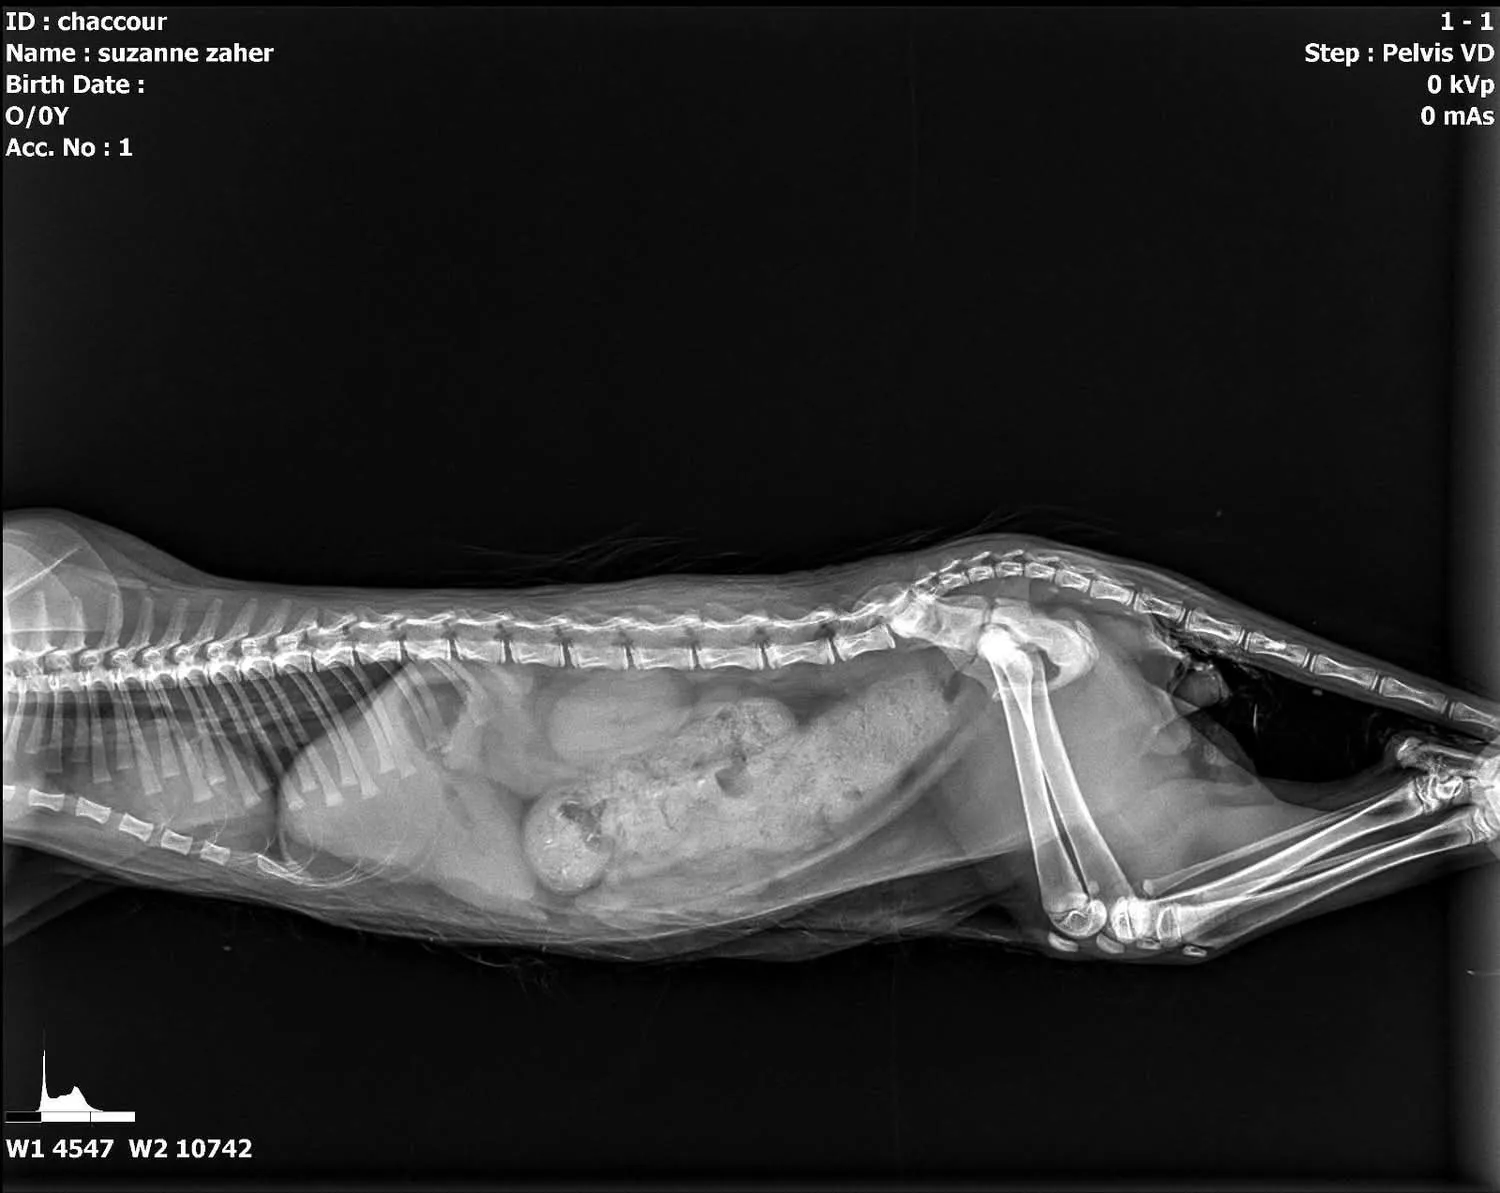

A surgical procedure for a pelvic fracture in cat